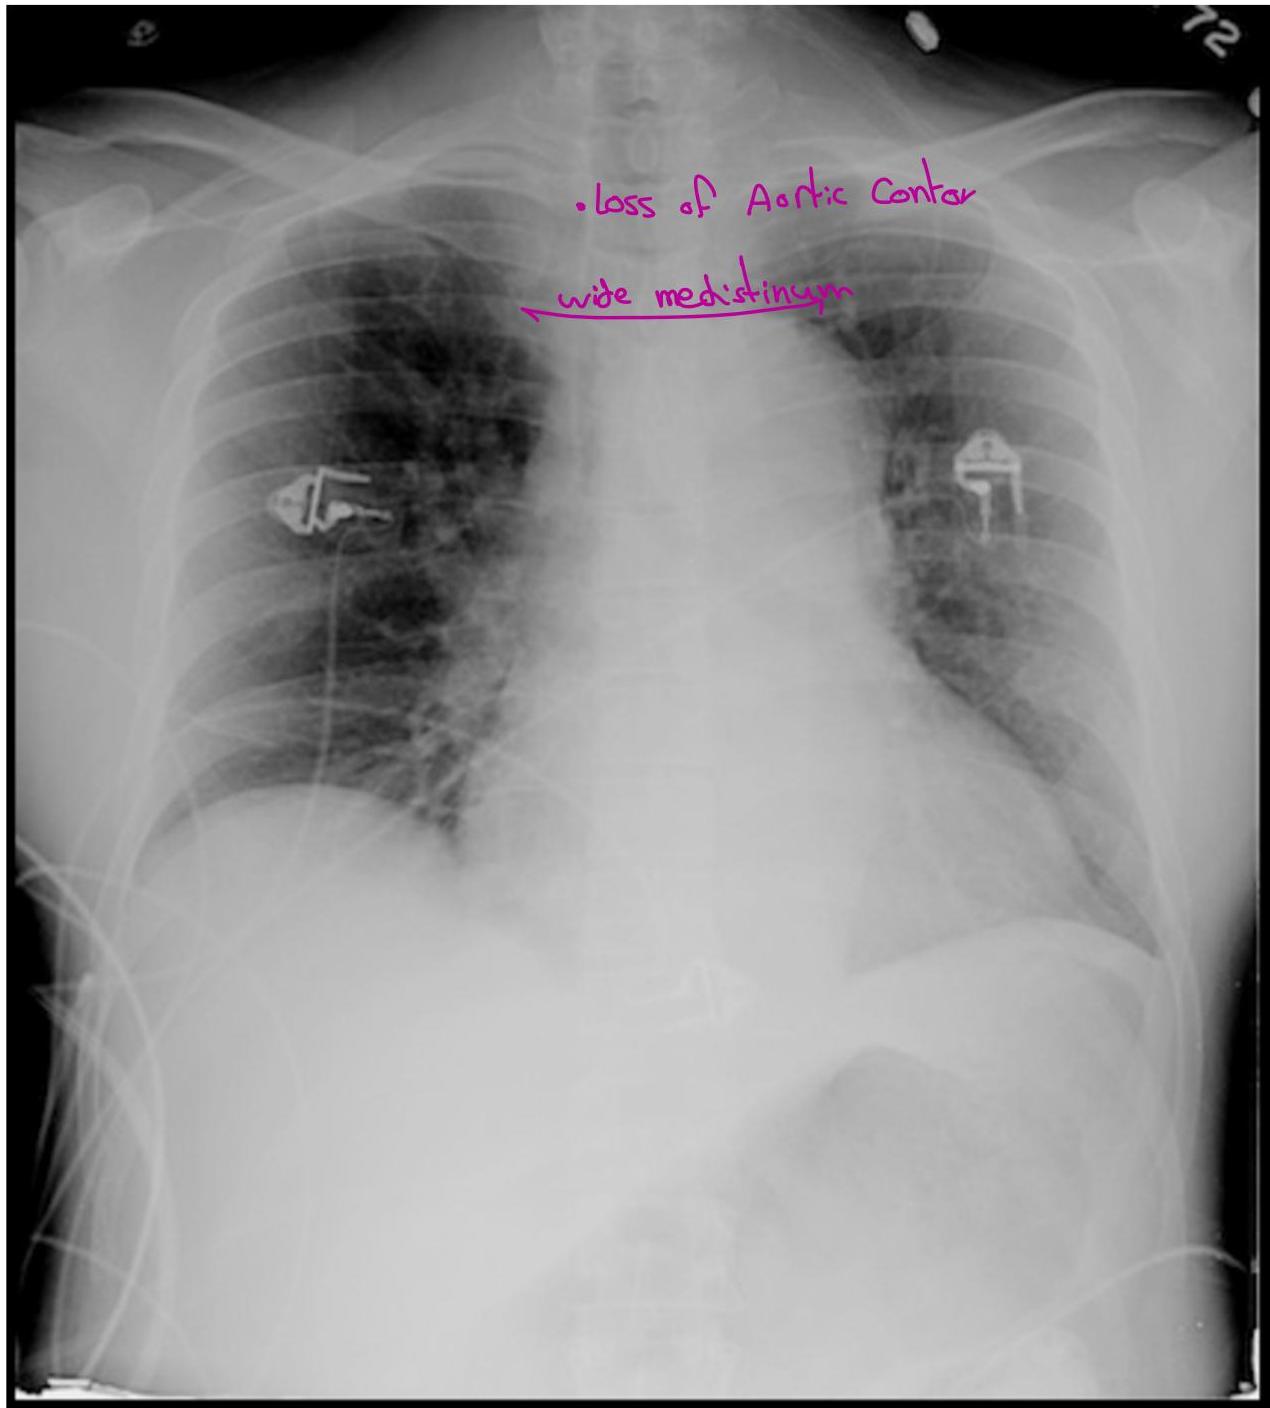

Case 4: Aortic Dissection

- Presentation: Crushing chest pain radiating to the back.

- Key Finding: BP discrepancy (R: 193/112, L: 160/99).

- Classification: Type A (Ascending - Surgical), Type B (any other part of aorta).

- Diagnostics: CXR, CT chest with contrast, MRI chest, TEE

Management of Aortic Dissection

- Type A dissection â Surgical

- Type B dissection â Medical

- Mainstay of medical therapy

- Pain control

- HR and BP control

- Goal HR = 60 beats/min, goal SBP = 100-120 mmHg

- Use IV beta-blockers (i.e. Labetalol, Esmolol)

- Can also use Nitroprusside for BP control

- AVOID Hydralazine